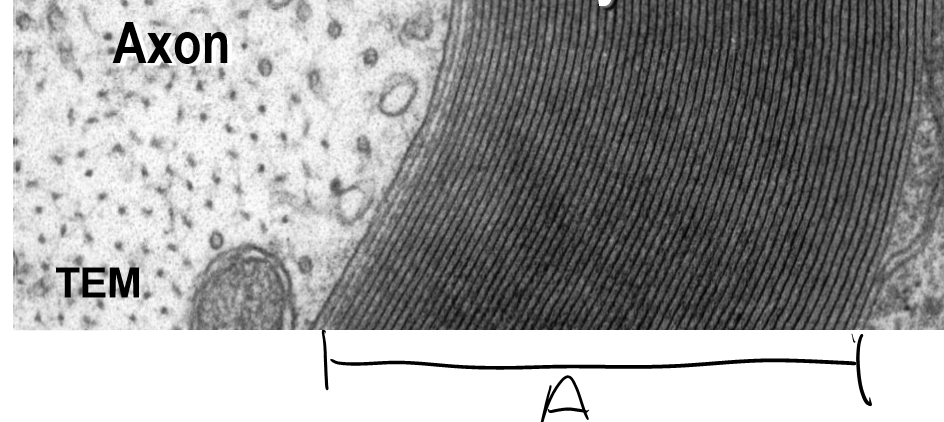

Q

What is the lable A indicating?

A

Myelin Sheeth